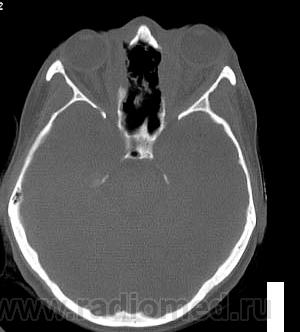

Просьба высказать мнения по поводу представленного патологического процесса.

Кажется, это уже было - гранулематоз Вегенера, если не ошибаюсь.

Гранулематоз Вегенера

Деструктивный процесс в полости носа и в пазухах может представлять собой гранулематоз Вегенера. Требуется тщательное собрание анамнеза, учет клинической картины, и разумеется, биопсия.